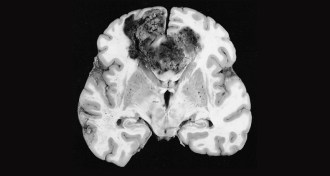

- 			 Health & Medicine Health & MedicineSmall molecule makes brain cancer cells collapse and dieA small molecule, Vacquinol-1, may provide a different way to target and kill cells in glioblastomas, a type of brain tumor.